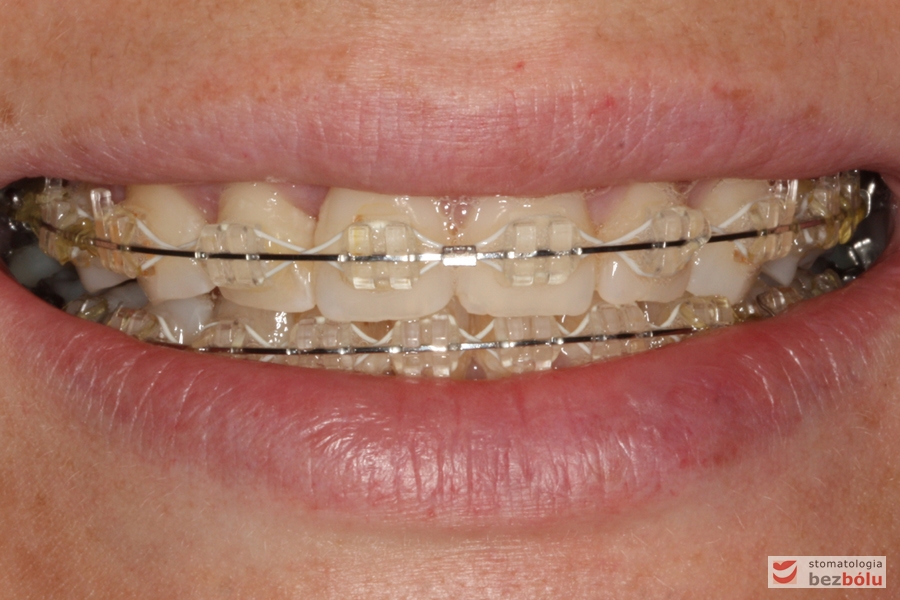

Cienkołukowy aparat estetyczny

Cienkołukowy aparat estetyczny - zastosowanie elastycznych wyciągów wewnątrzustnych

Cienkołukowy aparat estetyczny – zastosowanie elastycznych wyciągów wewnątrzustnych